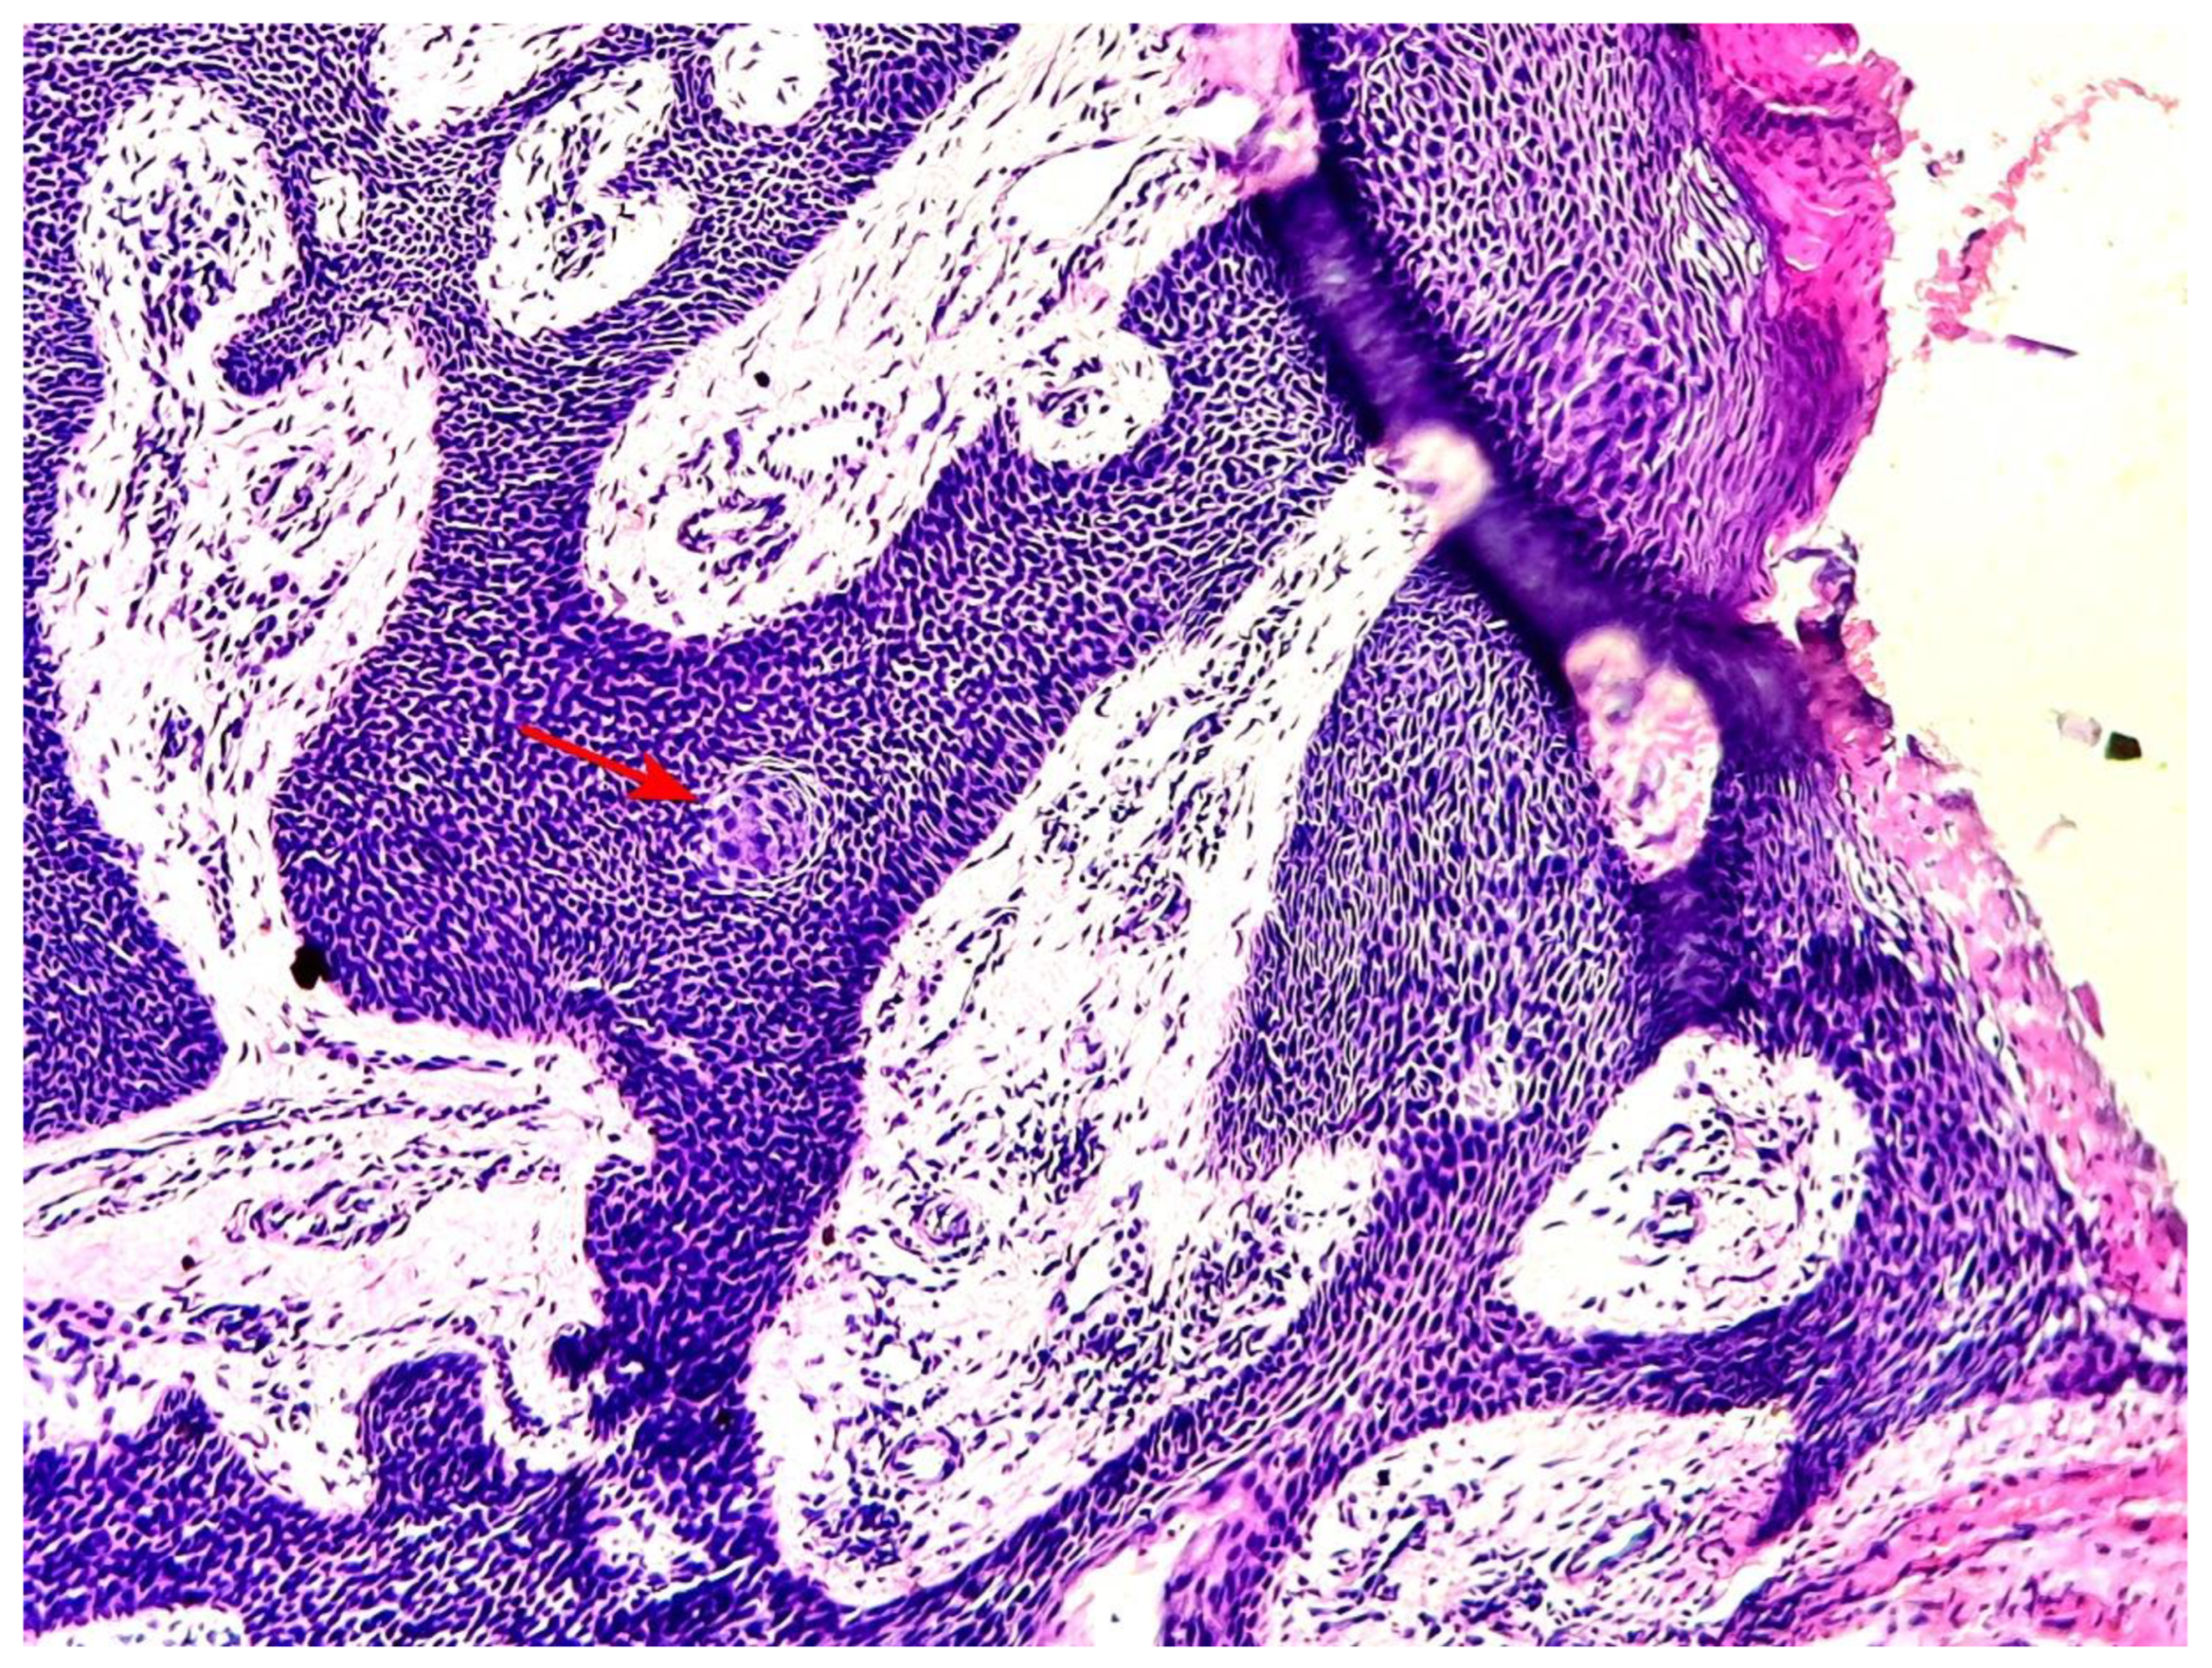

After serial additional sections, the final diagnoses of the 13 patients were: 10 classic poromas (CP) (76.9%) (Figure 2 a), 2 poroid hidradenomas (PH) (15.4%) and 1 dermal duct tumor (DDT) (7.7%) (Figure 2 b).

All cases were made of a variable mixture of poroid (uniform small cuboidal cells with round nuclei) and cuticular cells (larger cells with abundant eosinophilic cytoplasm), without cellular atypias, mitoses or stromal infiltration. The tumors’ stroma was fibro-hyaline and inflammatory in all cases, sometimes loose and myxoid. A broad epidermal connexion was observed in all cases of CP, whereas absent in cases of PH (cases 6 and 9) and DDT (case 12). Clear cells were observed in 7 cases (53.8%) (Figure 3).

Figure 2. a: Histological view of an eccrine poroma showing a dermo-epidermic tumor with predominantly poroid cells, broad-epidermal connexion and large anastomosing trabeculae disposed in a hyaline and inflammatory stroma (hematoxylin-eosin x 100) (case 2). b: Histological image of a case of DDT showing juxtaposed intradermal solid and cystic nodules without epidermal connexion. In one nodule a tiny ducal structure is readily apparent (small green circle) (hematoxylin-eosin x 100) (case 12).

Figure 6. A squamous eddy is seen in the image as focal maturation of poroid cells (red arrow) (hematoxylin-eosin x 100) (case 5).